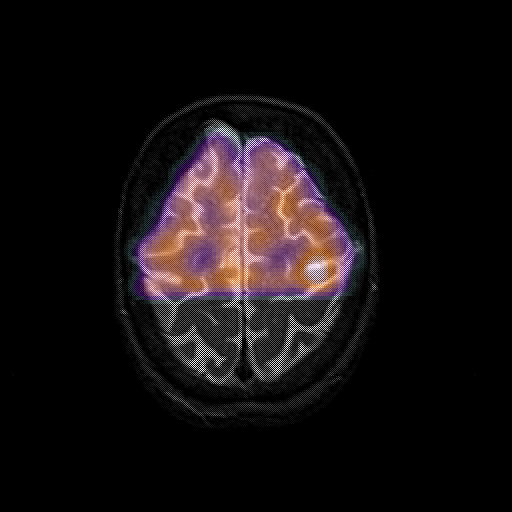

overlay 1: Slice 43

Slice 43

MRCBFCBF with

T1PDT2T1PDT2